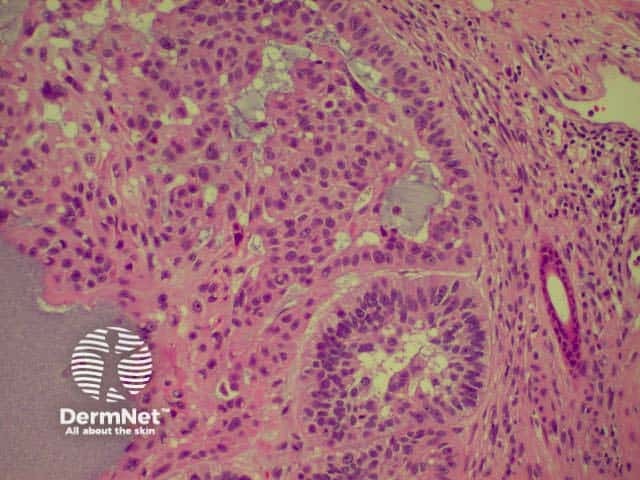

Invasive squamous cell carcinoma (SCC) is characterised by dermal invasion. Link to a clinical description of invasive squamous cell carcinoma.

SCC is characterised by proliferation of irregular nests of abnormal squamous cells arising from the epidermis and invading the dermis. Tumours are traditionally divided into well, moderately or poorly differentiated tumours by a subjective assessment of how significantly the tumour cells differ from normal keratinocytes. In general, the greater the degree of keratinization, the better differentiated the tumour is thought to be. Except in the case of very poorly differentiated tumours, this does not have a great bearing on prognosis. More important is the depth and irregularity of invasion, particularly the presence of perineural infiltration, which is associated with a much higher rate of recurrence if not widely excised. The site of the lesion is also important; tumours of the lips and ears have a considerably higher rate of metastasis to lymph nodes.

There are several descriptive variants of SCC including spindle cell SCC and acantholytic (or adenoid or pseudoglandular SCC). These mainly are of note due to the difficulty of diagnosing the tumour as SCC, but they may also imply a slightly worse prognosis. A further rare variant is verrucous carcinoma, a lesion in which the histology has a deceptively benign appearance in that there is very little cytological abnormality. Diagnosis in these cases may be delayed and the diagnosis may not be made until several biopsies have been performed. These tumours recur locally, but do not generally metastasise.

From the above comments it can be seen that the histological features of SCCs can vary, but in general are:

Pathology of SCC Pathology of SCC Pathology of SCC Pathology of SCC